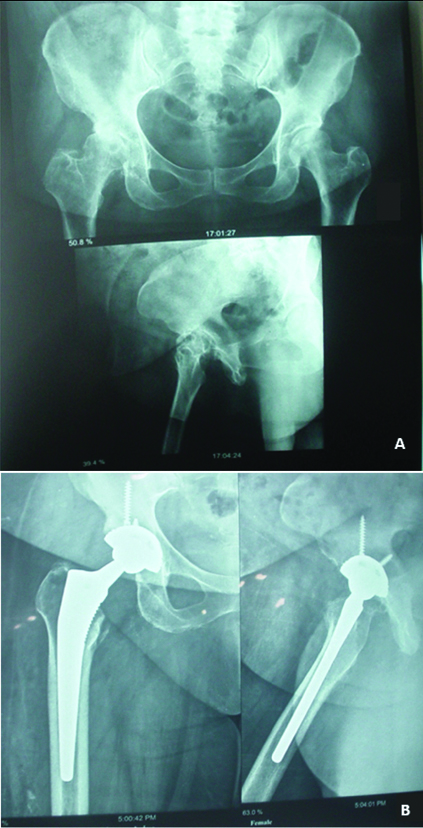

The HHS in patients at different times is presented in [Table/Fig-2]. As demonstrated, although mean HHS decreased during the first three weeks, after that, it was associated with an increase in the amount over time. The mean HHS before surgery was 49.69±5.00 and it progressed to 88.02±4.04 after 24 weeks (p<0.001). [Table/Fig-3] shows good outcome for a female patient, who was first presented with disruptive osteoarthritis of right femoral head, six months after the surgery. The patient was able to walk well and without lagging, and do all the necessary routine work with no pain and limitation.

(a) Patient with disruptive osteoarthritis of right femoral head before total hip arthroplasty; (b) After six months, the femoral and acetabular components were stable.